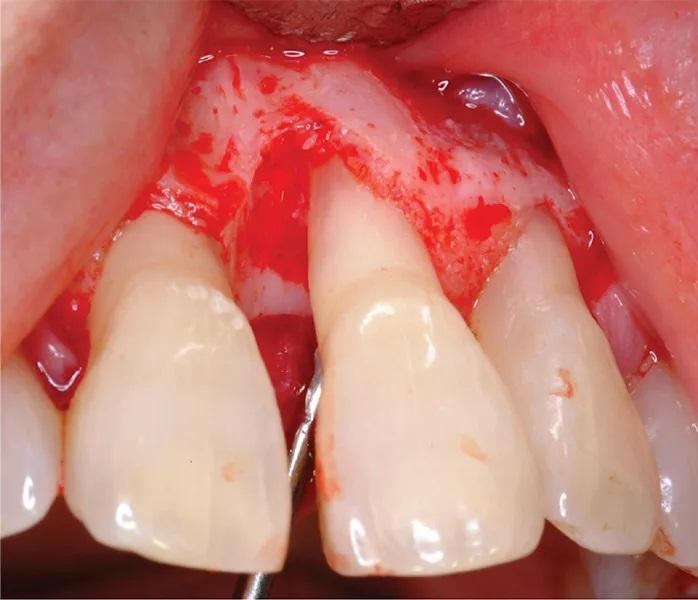

65-летняя некурящая пациентка с пародонтитом обратилась с костным дефектом на мезиальной поверхности верхнего левого центрального резца (зуб № 2.1) (Фото 1 и Фото 2). Зарегистрированный индекс подвижности (по Грейсу и Смейлсу) составил 2 степень, т.е. движение в вестибуло-лингвальном направлении на 1–2 мм. Во время процедуры пластики был отслоен слизисто-надкостничный лоскут, обнажен глубокий пародонтальный дефект (Фото 3 и Фото 4). Аутогенная кость была взята из ветви нижней челюсти и смешана в соотношении 1:2 с ДМБК (покрытый ОКФ, 100% губчатая кость) (Ti-oss, Chiyewon Co. Ltd.; распространяется как creos xenoform, Nobel Biocare). Полученный материал был смешан с высококонцентрированными тромбоцитами, полученными путем дополнительного центрифугирования БоТП (упоминается как концентраты тромбоцитов в протоколе, адаптированном автором), к которым были добавлены тромбин и кальций для образования коагулированной массы (Фото 5), использованной для заполнения дефекта (Фото 6). Показано, что тромбин и кальций in vitro и in vivo активируют тромбоциты для высвобождения факторов роста, тем самым стимулируя остеобласты, усиливая ангиогенез и способствуя миграции клеток.

Фото 3. Интраоперационное клиническое изображение, показывающее пародонтальный дефект.